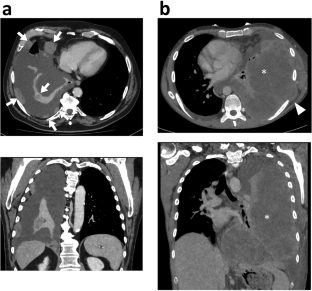

Of the 21 included patients (median age 48, range 30–74), 18 (85.7%) were male and 18 (85.7%) had a smoking history. Four main radiological patterns were identified depending on the location of the main tumor burden: mediastinal (n = 13), pleural (n = 6), cervical (n = 1), and retroperitoneal (n = 1). Median size was 120 mm (range 46–266). Characteristic CT imaging features of primary tumors included ill-defined margins (n = 21), heterogeneous enhancement after injection (n = 20), multi-compartment extension from mediastinum to lung apex, pleura, or neck (n = 20), compressive effect responsible for atelectasis (n = 11), vascular encasement (n = 16—5 superior vena cava syndrome), and esophagus invasion (n = 5). Primary tumors showed strong 18F-FDG avidity in eight patients with PET-CT. Necrotic lymphadenopathies were found in 19 patients, with a surrounding infiltrate in 13 patients. Metastatic locations at baseline mainly involved adrenal (n = 10), lung (n = 6), and bone (n = 5). Median overall survival was 5 months (range 1–13).

Most SMARCA4-DTS present with compressive and infiltrative chest masses with ill-defined necrotic lymphadenopathies. The diagnosis of SMARCA4-DTS should enter in the differentials of the radiologist, especially in the case of a rapidly evolving thoracic mass in young smoking males.

• SMARCA4-DTS, which is mostly located in the chest cavity, can compress and infiltrate all adjacent organs leading to superior vena syndrome, lung atelectasis, epiduritis, spinal cord compression, and esophagus invasion.

• SMARCA4-DTS typically demonstrates several ill-defined necrotic lymphadenopathies spreading in axillar, subclavian, cervical, mediastinum, and retroperitoneum.